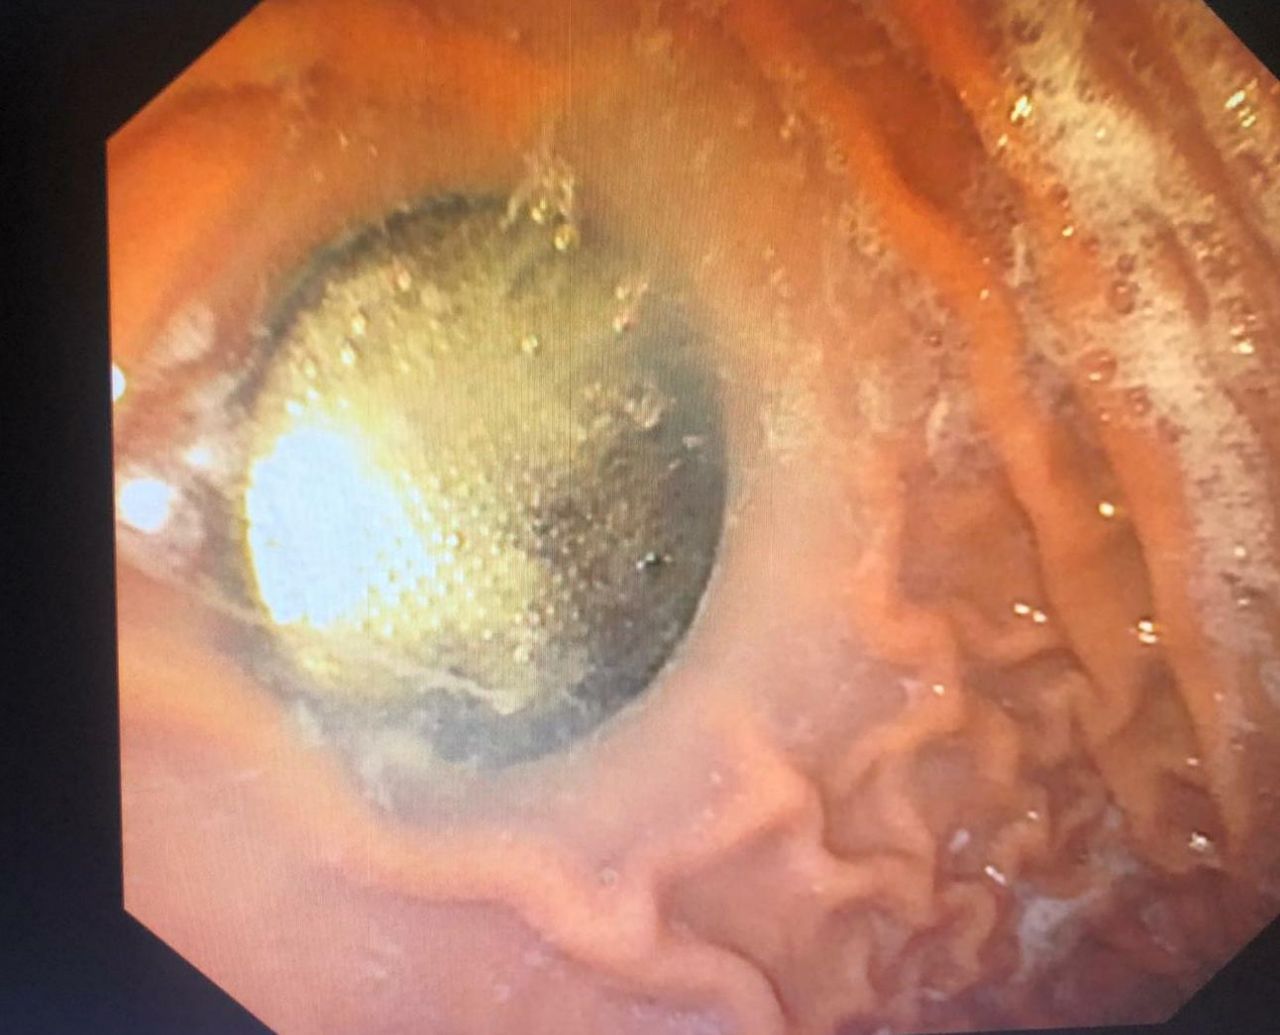

"הנזק הפוטנציאלי של סוללה נובע ממספר גורמים: לחץ מכני על איברים פנימיים, כמו במקרה של בליעת מטבע, הפעלת זרם חשמלי כתוצאה ממגע של דפנות מערכת העיכול עם שני הקטבים של הסוללה ודליפה של תוכן הסוללה (הסוללות מכילות בסיס חזק וכן מתכות כבדות כמו כספית, כסף, ליתיום)".

"במידה והסוללה תקועה בוושט, מדובר במצב חרום הדורש הוצאה מידית של העצם הזר ללא קשר אם הילד סימפטומטי. סוללות מסוג מסוים מצריכות התערבות פולשנית גם אם כבר הגיעו לקיבה. מדובר בפירוש במצבים שעלולים להגיע למצב מסכן חיים".